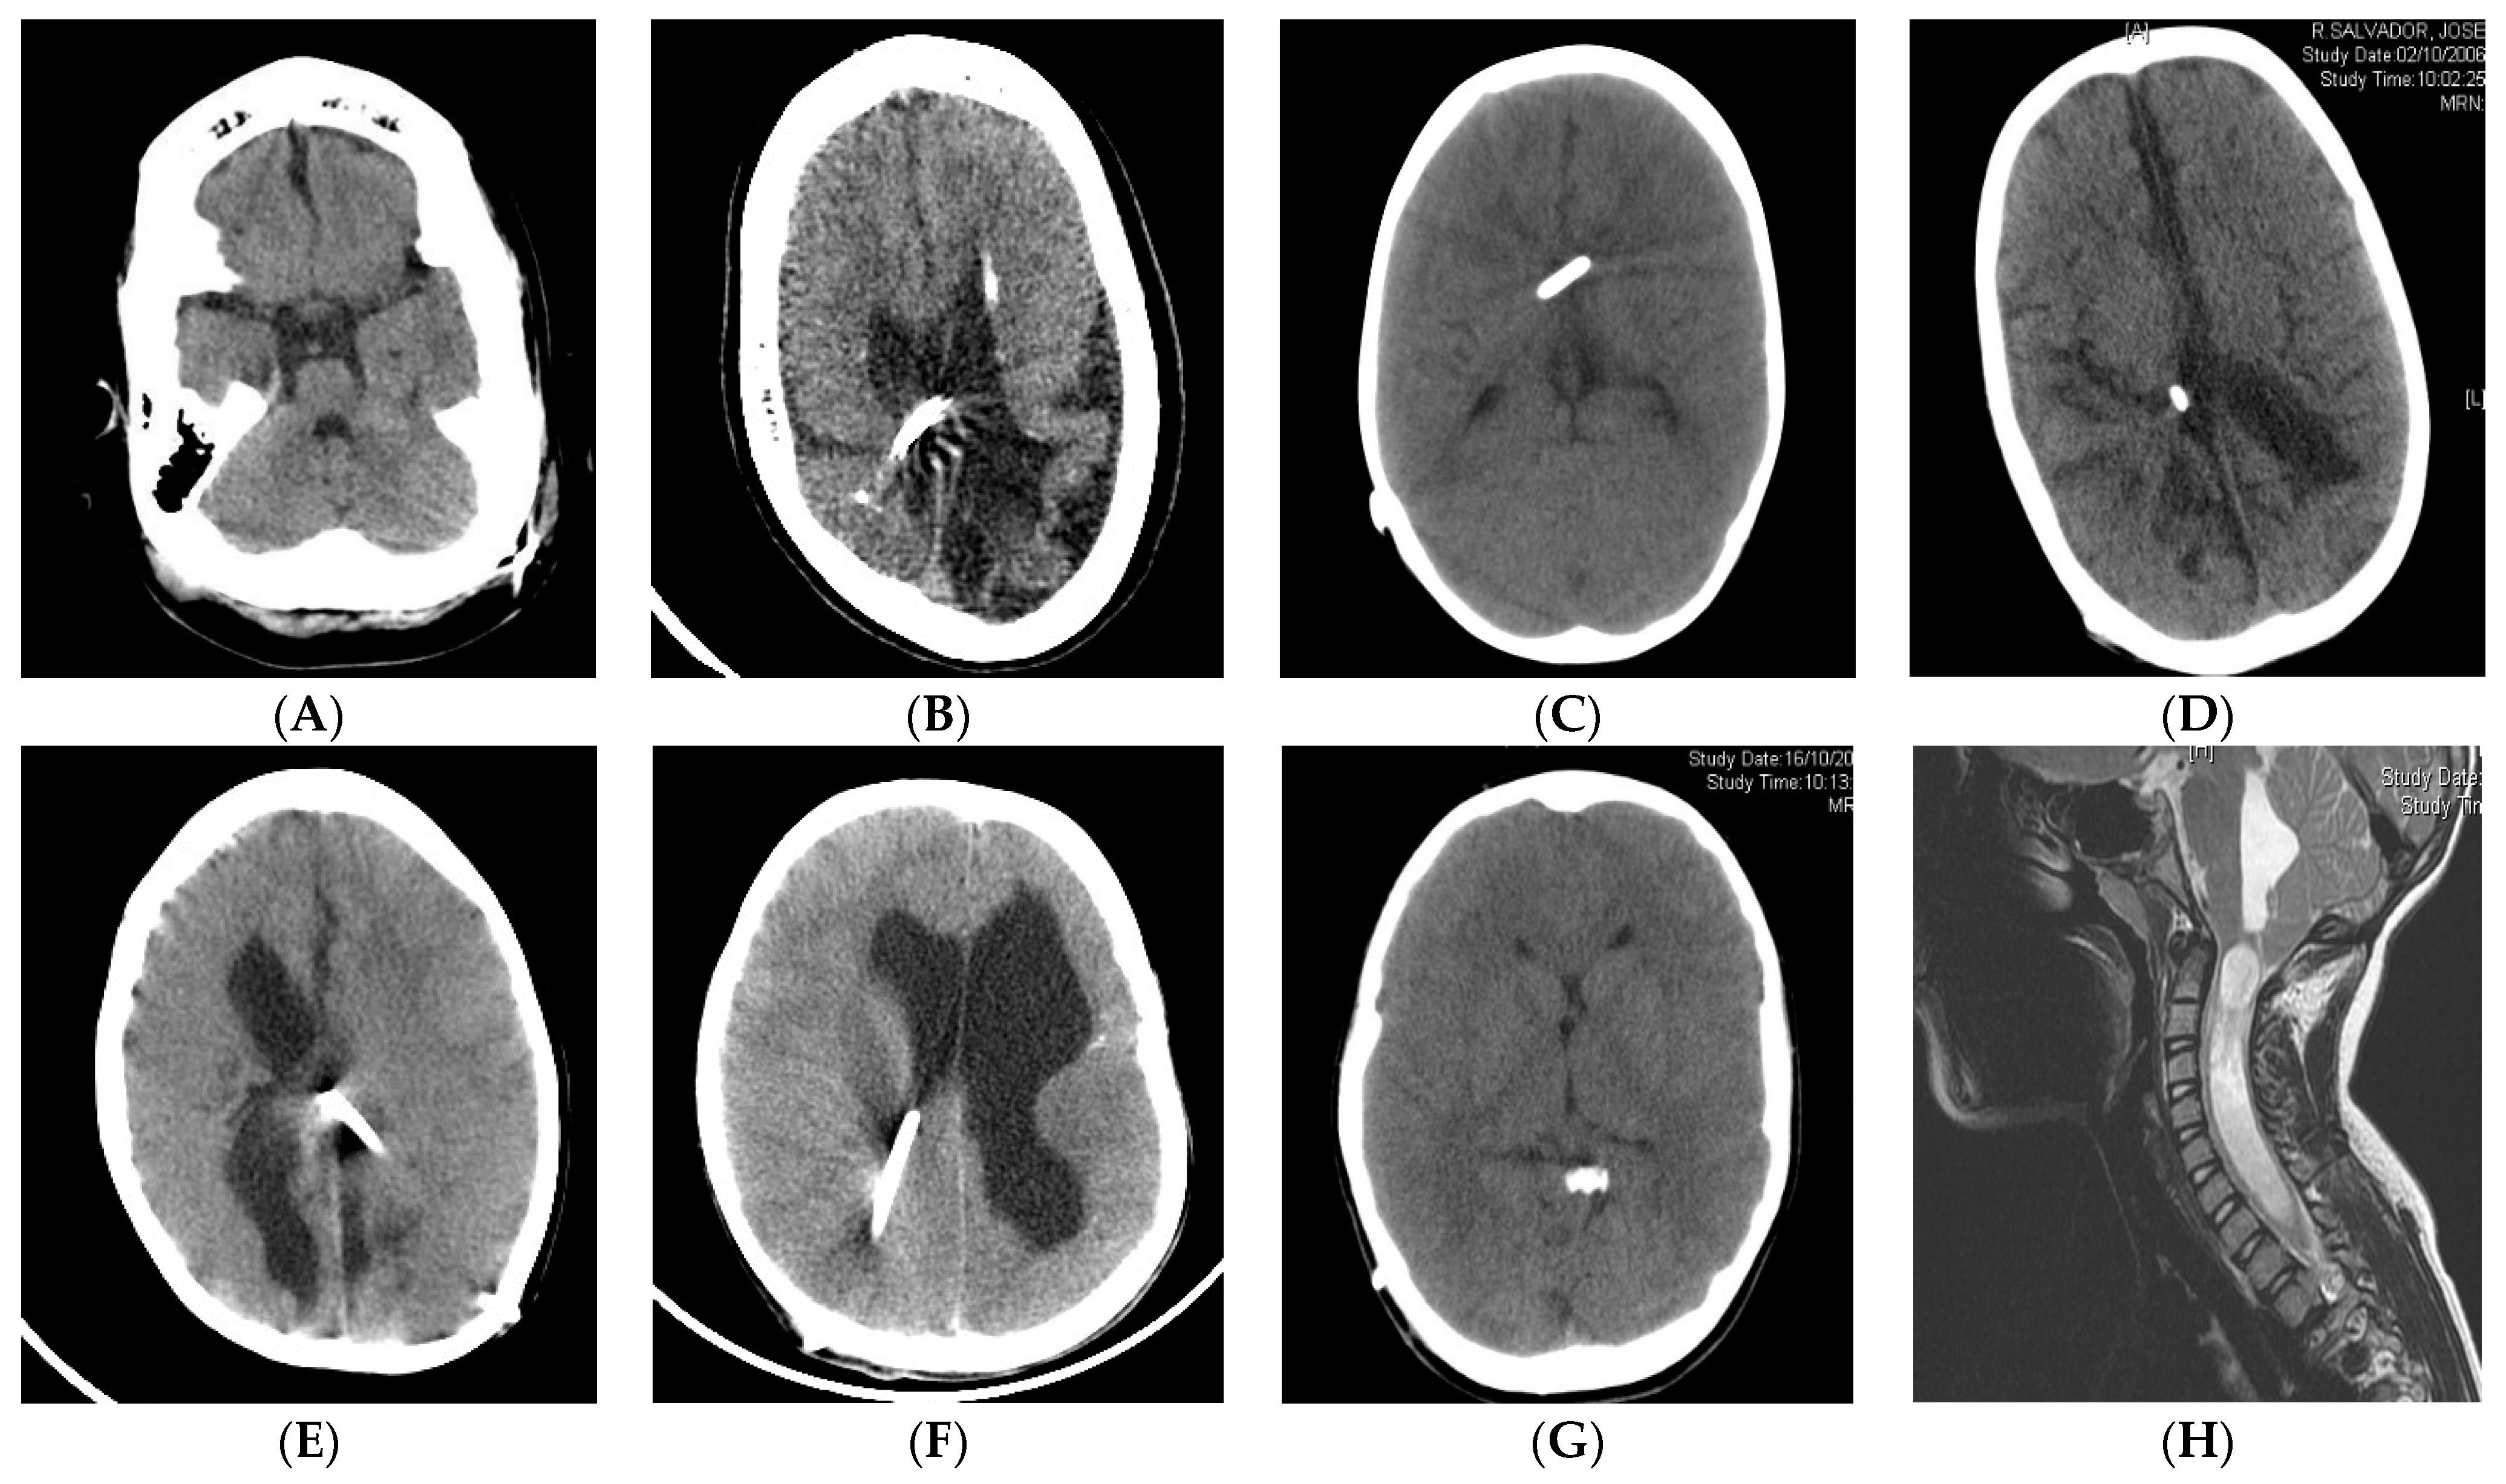

Chronic shunting in infants can lead to premature sutural fusion (suture sclerosis) and cranial vault or skull base bone changes, such as microcephaly, dolichocephaly, laminated thickening of the calvarium or sinus hyperpneumatization [67,68]. CCD may be present in the supratentorial and infratentorial compartments (acquired Chiari) [34,69,70]. Spinal canal stenosis may also be present [71,72]. Figure 1 shows some examples with the main radiological characteristics of shunt overdrainage.

Figure 1.

(A,B) A 5-year-old patient, shunted at birth after posthemorrhagic hydrocephalus. Postural symptoms. White matter damage with brain atrophy, small non-collapsed ventricles, extra-axial fluid collections, widened brain sulci, calcifications, laminated thickening of the calvarium, dolichocephaly and sinus hyperpneumatization. Shunt exchange with GV implantation was carried out, followed by clinical improvement. (C) An 8-year-old, shunted at birth after posthemorrhagic hydrocephalus. Complete ventricular collapse. Clinically, the patient presented sustained intracranial hypertension with papilledema, altered consciousness and bradycardia. Symptoms improved after shunt optimization by implanting an “in line” adjustable valve harboring a flow control device. (D–F) Ventricular collapse may be incomplete (D), unilateral (E) or focal (F). Non-collapsed areas may increase in size as a result of CSF isolation (E,F) and therefore can be considered for shunt transferring. (G) The catheter tip may be located outside the ventricular system (cisterns or extra-axial space). (H) Isolated fourth ventricle and syringomyelia as a result of sustained supratentorial overdrainage.